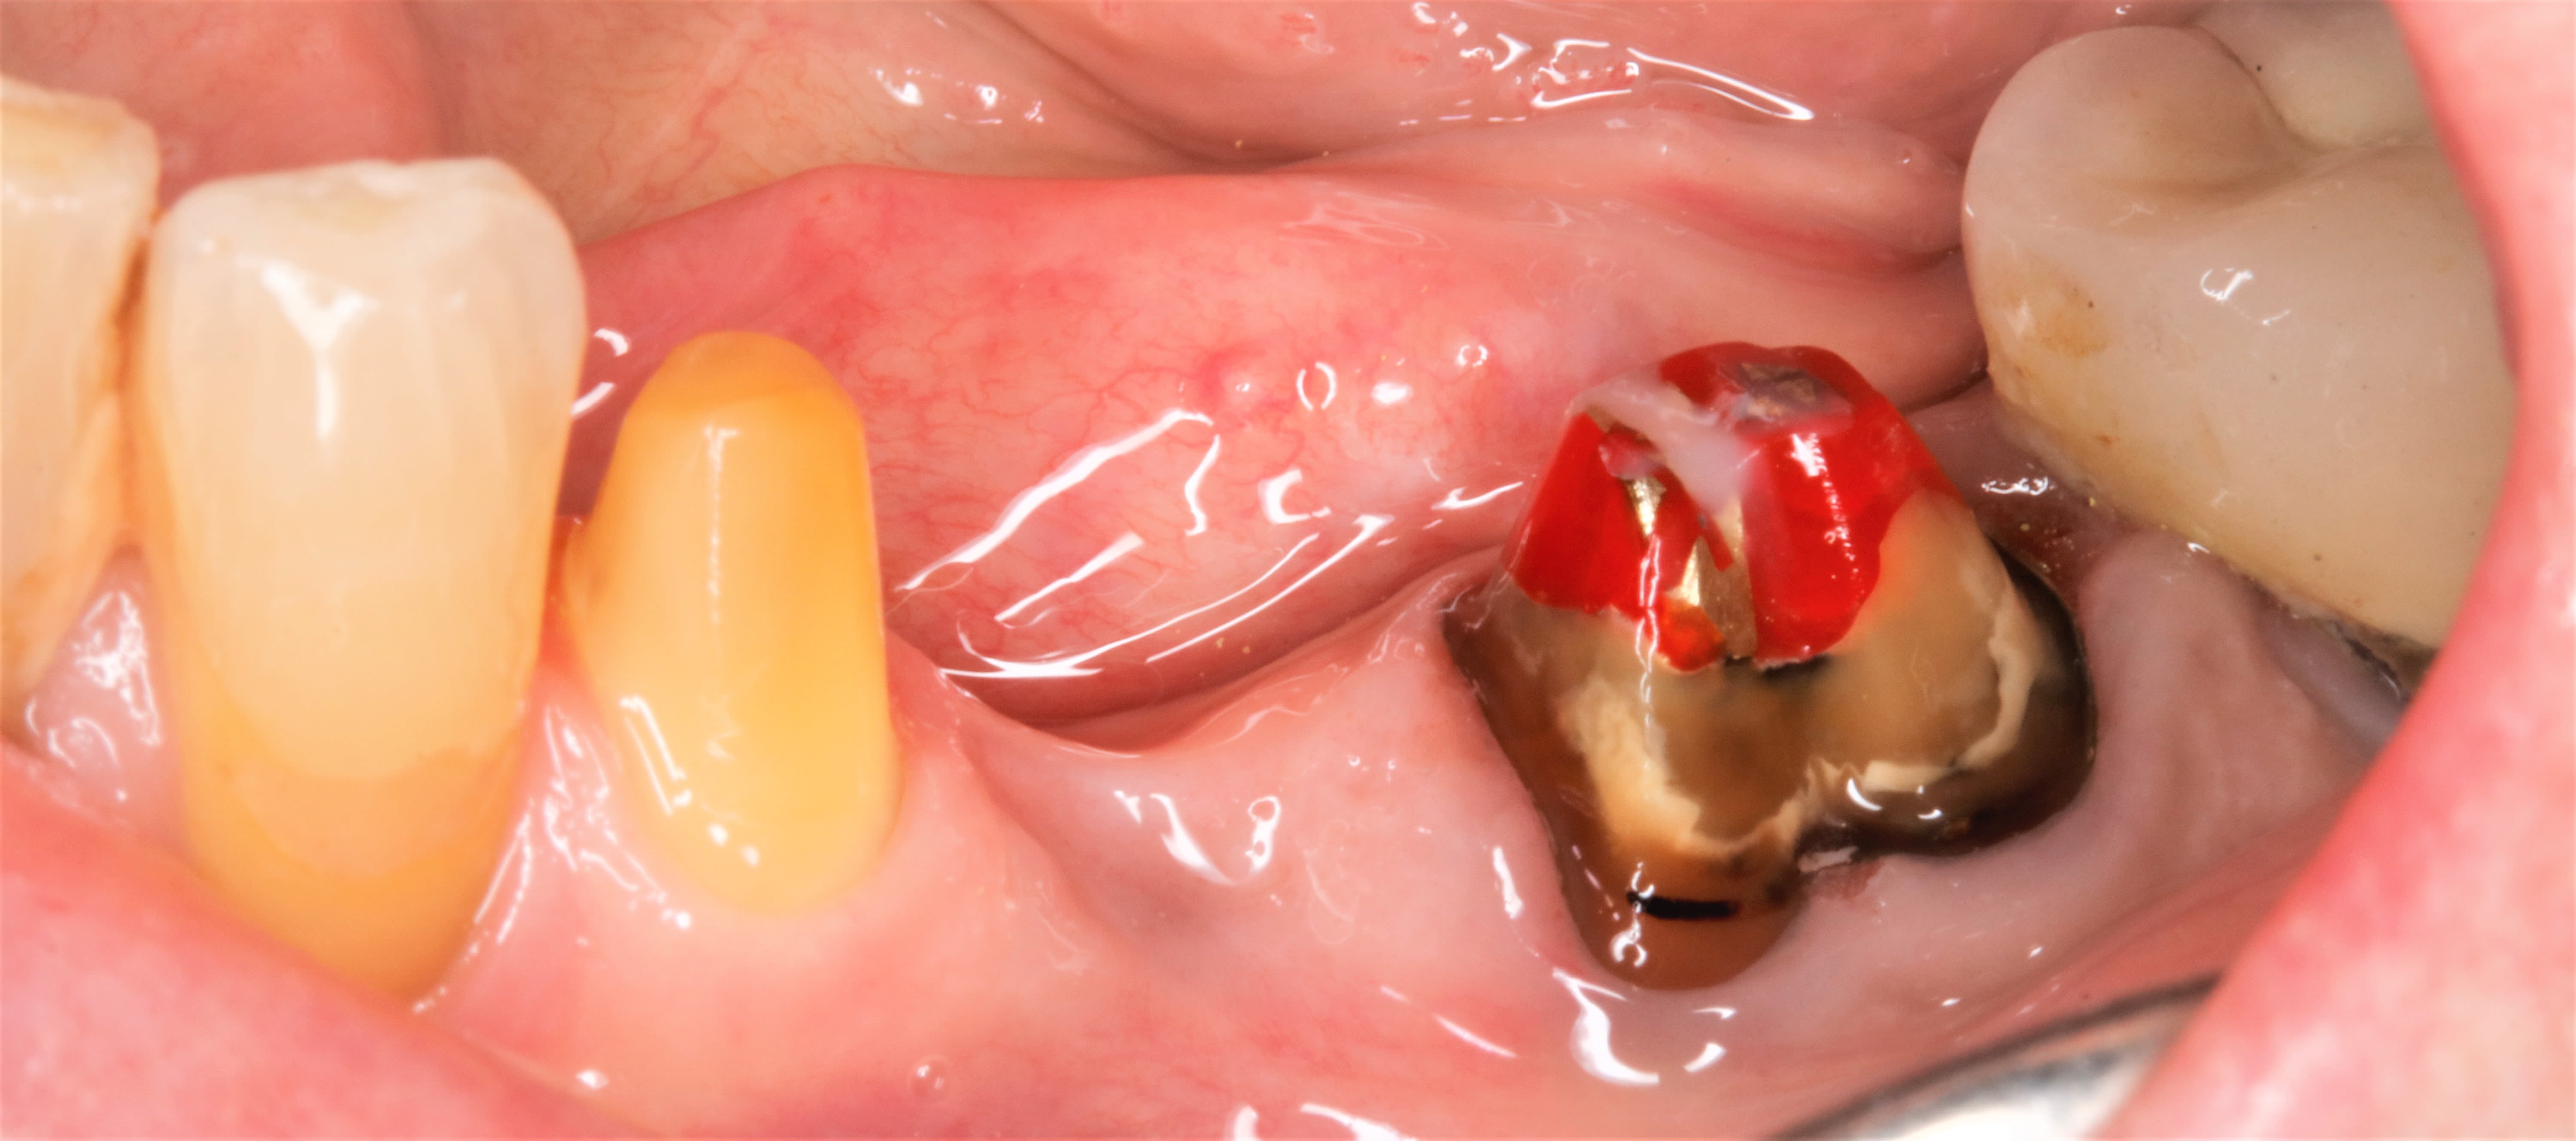

je cherche un reconstitution de moignon pas trop fluide

Apol mimesis

Un peu fluide mais auto et photo donc on peut le mettre en petites couches

Moi j en cherche un bleu ou rouge .

Que pensez vous du croma core de chez morita ?

Luxacore Z de DMG, auto photo, je l’utilise aussi pour coller les inlays, les contentions fibrées, les gros manques de matière...

polycore exotec

et si on se montait la sègue pour rien ? :-))

pas plus tard que t'aleur je viens de déposer une couronne où la reconstitution doit avoir ,pfff , bien+ de 25ans puisque ç était mon prédécesseur qui l' avait faite :. screw post et Duralay .

j ai repris la taille et zou un bridge .